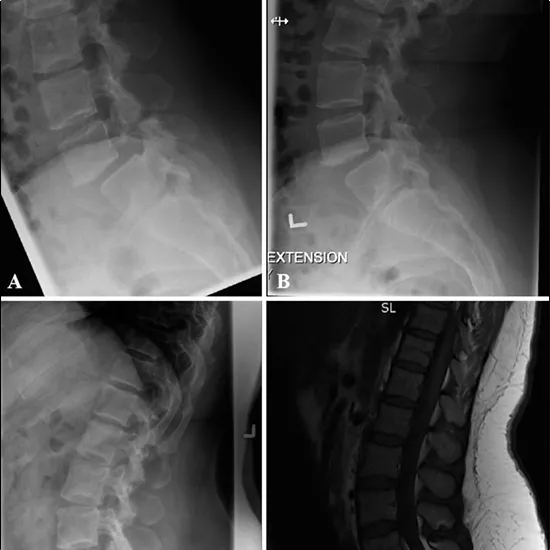

This examination employs X-rays to obtain pictures of the 5-vertebrae lumbar spine. This test is used to determine if the spine is unstable in spondylolisthesis, a condition that causes lower back discomfort. The patient is asked to lean back from the lower back for the extension view.